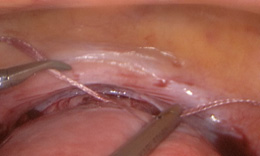

Cervical cerclage is a procedure in which a stitch is placed around the mouth of the womb (cervix) to help keep it closed and enable a pregnancy to go to term in women with a history suggestive of cervical insufficiency.